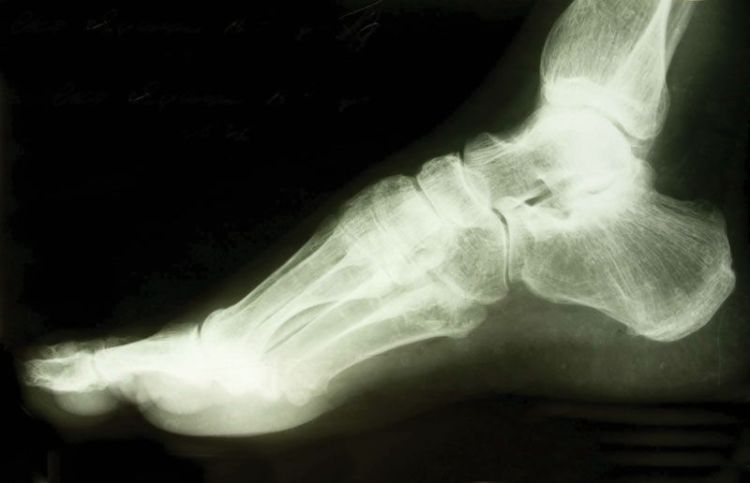

Huesos, calcificaciones, algunos tumores y otra materia densa se ven blancos o claros porque absorben la radiación. Los tejidos blandos menos densos y las fracturas en los huesos dejan pasar la radiación, lo que hace que estas partes se vean más oscuras en la película de rayos X.

Probablemente le tomarán radiografías desde varios ángulos. Si tiene una fractura en una extremidad, es posible que su médico quiera una radiografía de comparación de la extremidad no lesionada. Su sesión de rayos X probablemente terminará en unos 10 minutos. Las imágenes están listas rápidamente. Se desarrollan a partir de la película de rayos X o se graban en un CD para verlos en la pantalla de una computadora.